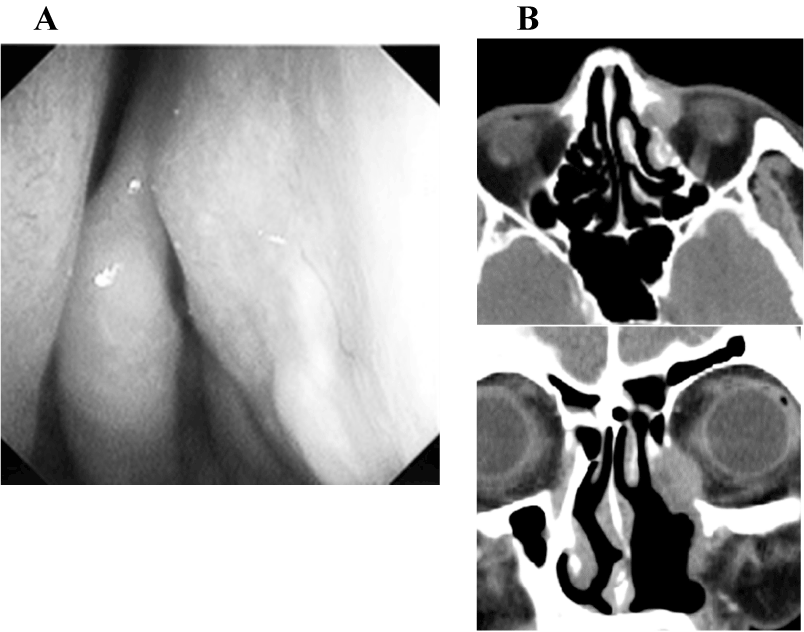

A 72 year-old female presented with right exophthalmous and diplopia. She had been treated for dacryocystitis for two years. On clinical examination, she was noted to have a firm mass inferior to the right medial canthas. The tumor was also easily visible in the right inferior nasal meatus (Figure1A). CT of the sinuses revealed an enhanced mass in the right lacrimal sac extensively involving the right orbit. There was also extension of the mass into the nasal cavity, the ethomoid sinus (Figure1B). Transnasal biopsy revealed moderately differentiated squamous cell carcinoma.

Figure 1A. A tumor was confirmed in the right inferior nasal meatus (arrows). Trans nasal biopsy was performed, which revealed moderately differentiated squamous cell carcinoma.

Figure 1B. Appearance of tumor on CT scan: axial CT scan shows enhancement of this lesion extending to the right orbit; coronal CT revealing the enhanced mass widely involving the orbit with bone destruction.